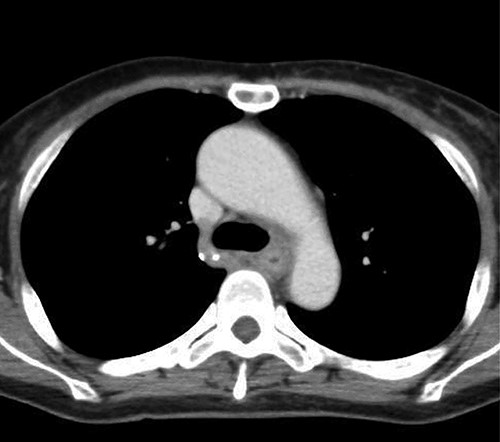

Preoperative computed tomography (CT) and barium meal studies were performed. The CT findings showed circumferential wall thickening with infiltrative change at the middle of the intrathoracic esophagus, with luminal dilation of the oral side of the stenotic esophagus (Figs 2, 3). The barium meal study showed no abnormal findings in the stomach (Fig. 4). Thoracoscopic esophagectomy was performed with the patient in the semi-prone position, followed by esophageal reconstruction using a gastric tube with the patient in the supine position. The operation was started with bilateral lung ventilation using a single-lumen endotracheal tube. A four-port thoracoscopic technique was used as follows: an observation port with a 10-mm scope was placed at the ninth intercostal space at the line of the inferior scapular angle, and two 5-mm ports and one 12-mm port for the intrathoracic procedures were placed at the third, fifth and seventh intercostal spaces, respectively, at the posterior axillary line (Fig. 5). Pneumothorax was created using 10 mmHg of CO2 to deflate the lung to achieve a better operative field. The pleura and connective tissue around the thoracic esophagus showed severe inflammatory and fibrotic changes. In particular, the middle thoracic esophagus was strongly adherent to the arch of the azygos vein and the tracheal bifurcation.

Upper gastrointestinal series showing the stomach; there were no specific findings in the stomach.